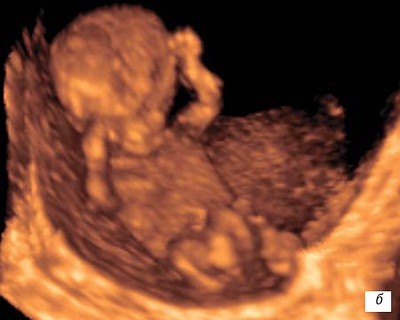

На 9-й неделе активно формируются нейронные связи. Плод начинает совершать непроизвольные движения: подергивания, сгибания. Частота сердцебиения в этот период может достигать 150 ударов в минуту — позже она снизится, когда контроль возьмёт формирующаяся нервная система.

Второй триместр: быстрый рост и развитие движений

К 14-й неделе плод достигает примерно 14 сантиметров. Укрепляются костные структуры, пальцы рук и ног полностью разделены, формируется мимика и движение глаз. Мозг координирует всё больше процессов, и плод начинает активно исследовать пространство — движениями, реакцией на свет и звуки.